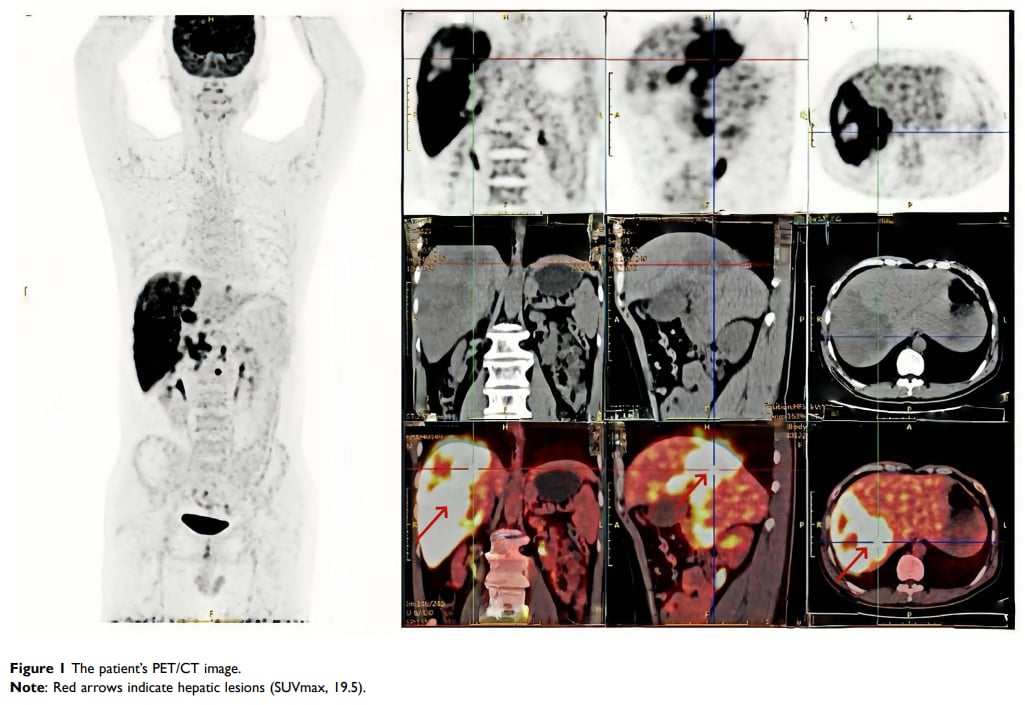

然而,平静的日子在2023年12月被打破。CT扫描显示,他的肝脏出现了多发占位性病变。为了明确病灶性质,医生于2024年1月对他进行了CT引导下的肝穿刺活检。初步的病理结果仅提示为腺癌,但由于免疫组化标志物表达不明确,无法确定其组织来源。会诊结果也未能完全排除胆管癌的可能性。紧接着的PET/CT检查进一步证实,肝脏内的多发病灶及周边淋巴结均为恶性转移的迹象。

▲图1 患者PET-CT影像